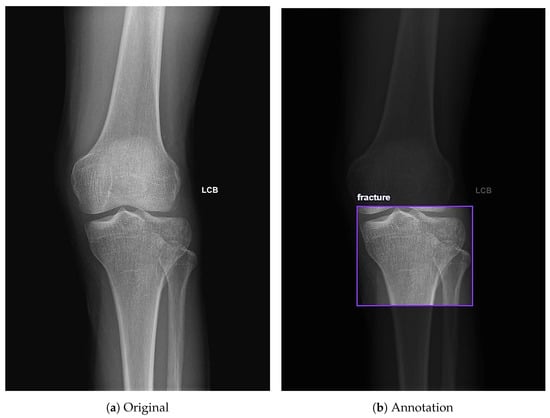

In addition to standardized lateral cephalometric radiographs, comprehensive assessment using dental cone-beam computed tomography (CBCT) and CT has become commonplace in the diagnosis and treatment of jaw deformities. Simulation based on cephalometr...